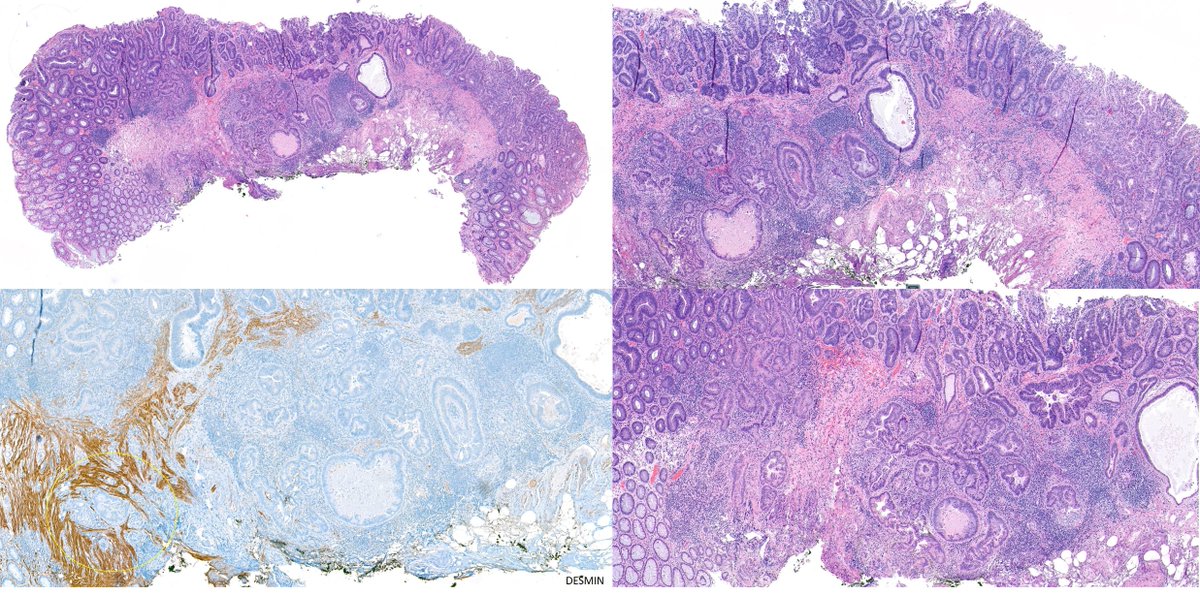

Rectal polyp. Pseudoinvasion or a pT1? A case of epithelial displacement vs pT1, before #GIpath short course at #USCAP23 What do you think?🤔

zucchiatti_'s tweet image. Rectal polyp. Pseudoinvasion or a pT1?

A case of epithelial displacement vs pT1, before #GIpath short course at #USCAP23

What do you think?🤔

Misplaced adenoma with high-grade dysplasia? Invasive adenocarcinoma -pT1? Wouldn't you love to know what the GI pathology gurus would call this? Do come to our short course - featuring Deepa Patil and Reet Pai #USCAP23 #GIpath